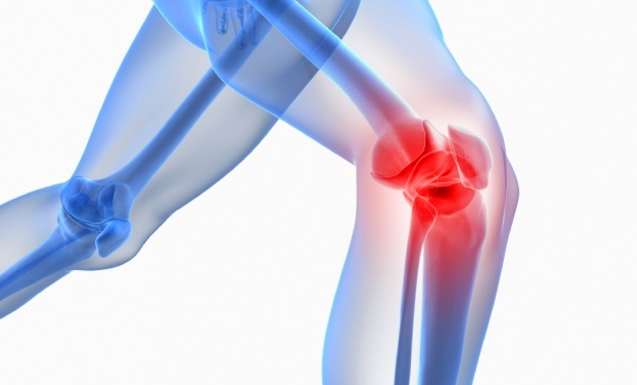

Knee replacement is among the safest and most successful surgical procedures. With this intervention, most patients can get back to their active and pain-free lives. On the other hand, mechanical issues like loosening, infection, or wear and tear might eventually cause a knee replacement implant to fail. Day-to-day tasks again become more challenging as the knee implant starts failing, causing pain, swelling, stiffness, or instability.

The following are the conditions that can lead to knee replacement failure and may necessitate revision surgery:

A revision knee replacement may be suggested only if non-surgical methods of symptom relief, like injections, bracing, physical therapy, or medication, do not work.